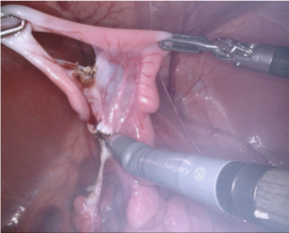

Our challenge was made up of 3 sub-problems. The first was binary instrument segmentation, where each frame was separated into da Vinci Xi instruments and a background class, which contained an ultrasound probe, surgical clips and porcine tissues. The second task was instrument part segmentation, where we scored the participants on whether they could correctly segment each articulating part of the instrument (see Fig. 3). Our final task was to segment and classify the instruments (see Fig. 4).

We provided the first 225 frames of 8 sequences as training data and kept the last 75 frames of those 8 sequences as test data. 2 of the full 300 frame sequences were kept as test sequences. Test labels were kept hidden from the participants. Our datasets contain 7 different robotic surgical instruments. The Large Needle Driver, Prograsp Forceps, Monopolar Curved Scissors, Cadiere Forceps, Bipolar Forceps, Vessel Sealer and additionally a drop-in ultrasound probe, which is typically held in the jaws of the Prograsp Forceps instrument. Samples from the training datasets are depicted in Fig. 2 and examples of the different instrument types are shown in Figure 3 and 4.